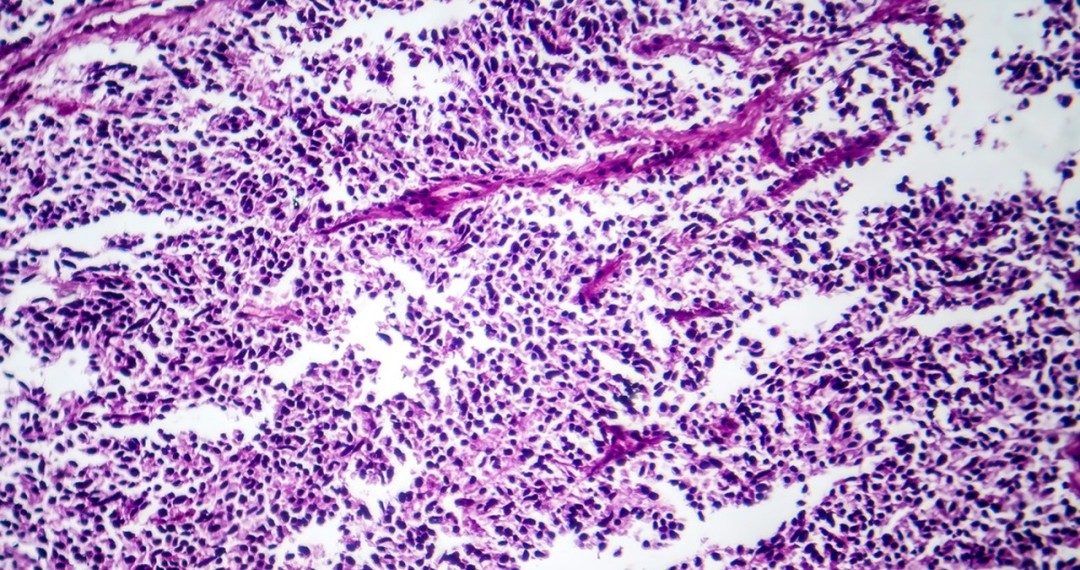

3.组织学转化

小细胞肺癌(SCLC)转化:约5%-15%的耐药患者发生谱系转化,失去EGFR依赖性,需依托泊苷+顺铂治疗。